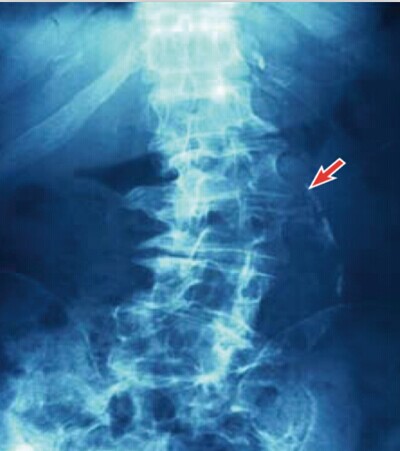

2. 骨代谢紊乱:发生骨溶解/骨质疏松/骨折(图二)

(图2)